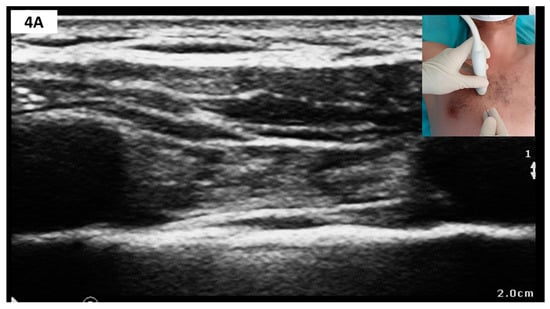

Sonoanatomy and Block Technique (Figure 4)